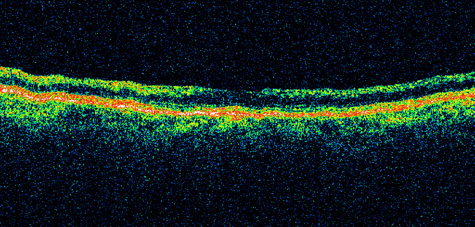

CENTRAL RETINAL ARTERY OBSTRUCTION Central retinal artery obstruction is one of the most sudden and dramatic events seen by ophthalmologists and was described as early as 1859.1 Although there have been numerous clinical and experimental studies of the pathophysiology of central retinal artery obstruction and although these studies have been augmented by the introduction of intravenous fluorescein angiography in the 1960s, the disease still has a relatively poor visual prognosis. The clinical picture is typically striking. Patients present with a sudden painless loss of vision. The appearance of a cherry-red spot in the fundus is characteristic (Fig. 1).2 The cherry-red spot appears because soon after obstruction of the blood flow to the inner retina, the normally transparent retina becomes opaque and blocks the brownish-red color from the underlying choroid, which is still supplied by blood. Because the retina overlying the foveola is relatively thin, however, the normal color of the choroid is still visible in this area.3,4 Although characteristic, the cherry-red spot is not pathognomonic for central retina artery obstruction.5 Sometimes the characteristic cherry-red spot does not develop; there may be only a slight accentuation of the brownish-red color in the foveola.4 It is not known how long it takes this cherry-red spot to appear, but in a primate model, it has appeared as early as 30 minutes after obstruction.6 An afferent pupil defect is usually present.2 With obstruction, virtually all eyes have narrowing and irregularity in the arteries and there is frequently an irregularity in the caliber of the retinal veins.2,4,6,7 Segmentation (boxcarring) of the blood column frequently develops; this segmentation is particularly noticeable in the veins and can be seen as a to-and-fro movement of the blood elements.3,4 Retinal hemorrhages, however, are not characteristic of central retinal artery obstruction.7 With time, the retinal opacity diminishes, generally leaving an optic nerve that is atrophic (Fig. 1). Frequently, thinned retinal arteries and veins also remain.7,8 No foveolar light reflex is evident, and a finely pigmented appearance of the macula is typical.7 In some cases, arterial collaterals develop at the optic disc.9–11 Rarely, anatomoses that exist between the central retinal artery and the ciliary arteries become visible as preretinal loops (Nettleship collaterals) after an occlusion at the edge of the disc.12,13,378In approximately 20% of patients, an embolus is evident somewhere in the arterial system.14 Emboli are discussed later. Intravenous fluorescein angiography is useful in showing the details of the abnormal circulation of a central retinal artery obstruction (Fig. 1). The principal abnormality is the delay in the appearance of the dye in the central retinal artery and its branches.2 Rather than the central retinal artery and its branches filling rapidly, considerable time may elapse before the entire arterial system is filled.15 The filling of the retinal arteries is often abnormal, with the fluorescein partially filling an artery (a dye front) or hugging the vessel wall, as in normal venous filling.15 Segmentation of the blood column is often well defined on fluorescein angiography.15 Venous filling is usually slowed and occasionally the dye does not progress beyond laminar flow during the study.14 In approximately 10% of eyes that have central retinal artery obstruction, there are abnormal choroidal filling defects, reflecting posterior circulation obstruction. These defects can occur even in patients who appear to have a typical central retinal artery obstruction.14 Leakage of dye from the vessel walls is not normally seen except at the site where an embolus lodges within a retinal artery.16 With time, the flow within the artery and its branches is reestablished and the appearance of the intravenous fluorescein angiogram may return to normal. The electroretinogram (ERG) is usually abnormal in central retinal artery obstruction. The b-wave is reduced, indicating a marked abnormality in the circulation of the inner retina.17,18 The a-wave, indicating normal photoreceptor function, is preserved or accentuated. There does not appear to be a good correlation, however, between the extent of b-wave abnormality and the degree of retinal function,3 although Yotsukura and Adachi-Usami420 reported that the b-wave amplitude increased with visual improvement. The photopic negative response (PhNR) shows severe depression in this condition reflecting the significant loss of the ganglion cells and their axons.377 The electrooculogram may be either normal or abnormal. Visual field defects are usually profound but either occasionally a small portion of the temporal peripheral visual field remains or the patient has a large central scotoma.3 The onset of obstruction occurs most often between the hours of midnight and 6 AM, with the second most common period being between 6 AM and noon.2 Most patients with central retinal artery obstruction complain of a sudden loss of visual acuity in the affected eye; most of these patients present with visual acuity ranging from finger-counting to light perception.14 Only about 5% of patients have visual acuity of no light perception and most of these have involvement of the posterior ciliary circulation, which can be seen on either intravenous fluorescein angiography or electrophysiology.14 Without a partial central retinal artery obstruction or a spared cilioretinal artery (to be discussed), it is unlikely that any patient will have initial visual acuity better than finger-counting.14 With or without treatment, most eyes retain visual acuity of finger-counting to light perception. Patients with a spared cilioretinal artery do not seem to have a follow-up visual acuity that is significantly different from those without a spared cilioretinal artery.14 Central retinal artery obstruction is caused by the disruption or cessation of blood flow to the central retinal artery, its branches, and the retinal layers supplied by those vessels. The inner two thirds of the retina derives its blood supply from the central retinal artery and its branches; the outer third of the retina is supplied from the choroidal circulation.19–21 The central retinal artery and its branches function as an end artery, and with the exception of a few anastomotic connections between the retina and the ciliary circulation at the optic disc, there are no other anastomoses.19 No intrinsic retinal vessels are present in the fovea because the inner retinal layers are not present in this area.19 Histopathologically, when a central retinal artery obstruction occurs, the retina initially becomes edematous. With time, all the retinal layers supplied by the central retinal artery and the artery's branches, including the nerve fiber layer, ganglion cells, inner plexiform layers, and the inner portion of the inner nuclear layer, are lost.20 In trypsin digest preparations after obstruction of the central retinal artery, the greatest change is in the capillary bed,22 where extensive ischemic changes take place. Usually, little attempt is made to repair the retina with gliosis or neovascularization.20 The most common site of obstruction of the central retinal artery is at the level of the lamina cribrosa.20 Clinically, it is possible to examine the blood flow velocity in the central retinal artery in a noninvasive manner, using a variety of techniques.21 The most useful appears to be color Doppler imaging, providing simultaneous Doppler and B-scan ultrasound images of the optic nerve head, which primarily represents flow in the central retinal artery.23 Studies using this technique demonstrate a marked reduction of or no blood flow in the central retinal artery with an acute central retinal artery occlusion that returns to normal with time.24 Characteristics of the retinal blood flow can be measured clinically with retinal Doppler velocimetry.385 This is an instrument that can measure the blood column diameter, the centerline blood velocity, and the blood flow in major retinal vessels. However, when evaluating the blood flow in the optic nerve, choroidal, and retina, the Doppler laser flowmetry is more sensitive to the blood flow in the superficial layers than in the deeper layers.410 Masaoka and colleagues384 studied the hemodynamic changes in the retinal circulation with a scanning laser ophthalmoscope and intravenous fluorescein angiography. This technique allows the assessment of erythrocyte velocities and movement with high resolution continuous images and is a useful technique for the evaluation of hemodynamic changes in vascular occlusions. Analysis of the retinal nerve fiber layer by one of the confocal laser scanning tomography techniques can provide information about a central retinal artery occlusion. Foroozan and co-workers383 studied patients with a central retinal artery occlusion within 1 week of occlusion with a scanning laser polarimeter. Diffuse attenuation of the retardation of the nerve fiber layer surrounding the optic nerve was seen in all eyes studied. Four patients were scanned in follow-up at intervals ranging from 1 week to 6 weeks; all had unchanged studies.383 Optic coherence tomography (OCT) of an acute central retinal artery occlusion shows a slight increase in the thickening of the retina and reflectivity of the inner layers of the retina that correspond to the opacity seen clinically (Fig. 1).409 With time, the disc becomes atrophic and the retina thinner. Experimental studies of central retinal artery obstruction in the cat25 and the rhesus monkey26–28 have increased our understanding of arterial obstruction. The most clinically relevant finding is that there is a period in which a total lack of blood flow (ischemia) to the inner retina can be tolerated; that is, if the blood flow is not obstructed longer than this period, visual function may return to normal. This critical time in the cat eye is 90 minutes,25 and in the young, healthy rhesus monkey it is 100 minutes26–28—any longer than this and the histologic changes are irreversible and the animal has permanent visual loss. Hayreh and co-workers379,380 have repeated this experiment to determine how long the retina can survive central retinal artery occlusion in middle-aged and elderly rhesus monkeys, a situation that might be more applicable to the human situation where most occlusions occur in older patients. That study showed that an occlusion of less than approximately 100 minutes produced no permanent damage and that an occlusion of longer than 240 minutes produced massive and irreversible retinal damage. It is not known why the older monkeys had a longer retinal survival time with occlusion of the central retinal artery than younger monkeys. Because there is no evidence that the monkey and the human have different retinas,379 the studies by Hayreh and co-workers have implications for studies that attempt to treat central retinal artery occlusion. Any treatment of this condition will almost certainly have to be initiated within 100 to 240 minutes, assuming the occlusion is total, or the patient will likely have permanent damage to the retina, regardless of treatment. On average, central retinal artery obstruction occurs in patients who are in the fifth or sixth decades of life, with the age range varying from 17 to 84 years. Fewer than 10% of patients are younger than 30 years of age.14,29,30 In some cases, the cause of central retinal artery obstruction is relatively clear, such as when due to a visible embolus. In other cases, however, especially when found in association with a systemic disorder such as diabetes, the association is less clear. Table 1 lists some of the conditions associated with central retinal artery occlusion. Arteriosclerosis is probably the most commonly associated systemic condition. With the progressive buildup of subendothelial atheromatous material, the lumen of the central retinal artery becomes narrowed over time and eventually may become occluded.20 This association is inferred because most patients with central retinal artery obstruction are in the fifth to sixth decades of life, when atherosclerotic changes are expected. TABLE 1. Conditions Associated With Retinal Arterial Obstructions